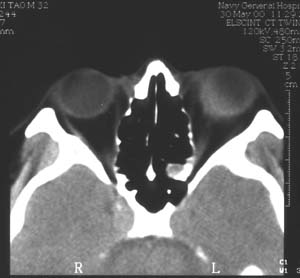

图1 患者男性,32岁。99年8月发现左眼球突出,当时按眶内炎症治疗无效99年12月左眼开始充血,反复发作(后来仅间隔1-2天),头痛。曾按“结膜炎、眼眶炎症”等治疗无效。2000年4月经CT检查发现左眼球外侧肿物,诊断:眼内肿物、眶内炎性假瘤?随来我院。入院检查:视力(戴镜)右眼1.0,左眼0.3,不能矫正。左眼睑肿胀,结膜混合充血,结膜下血管怒张(图1)。角膜正常,屈光间质清楚。眼底为高度近视眼底表现(-10D),眼球壁内下方6:00-9:00自视盘下方开始隆起(约+6D)。眼球突出4mm。B超及标准化A超显示左眼球内下方及下方巩膜肥厚,最厚处达7mm,可见明显筋膜囊水肿(图2)。CT显示左眼球内下方巩膜增厚,并向眼内隆起,筋膜囊水肿(图3)。

图3 CT显示左眼球内下巩膜增厚并向眼内隆起,合并筋膜囊水肿边界欠清楚